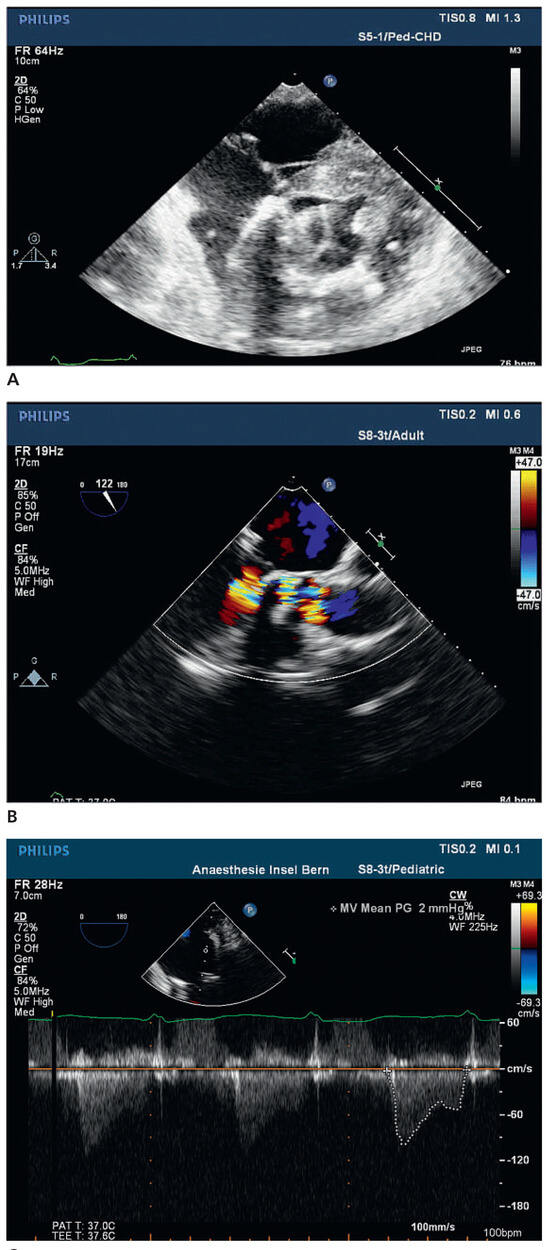

We report on the worldwide first implantation of a transcatheter valve in mitral position using a surgical approach to treat severe combined mitral valve disease, complicated by massive calcifications of the whole mitral anulus. The management of suc...